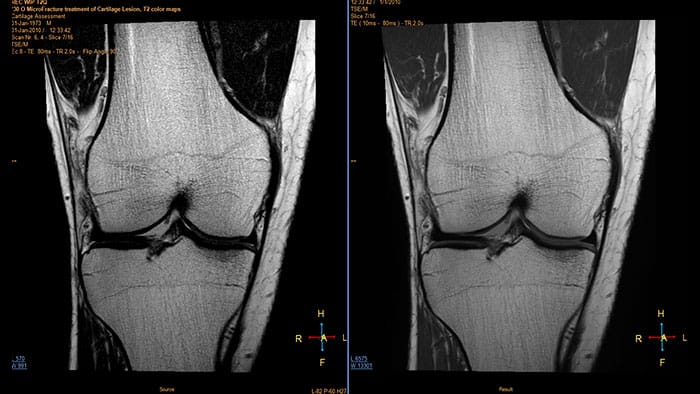

MR Cartilage Assessment

Visualize cartilage structures

Enables the visualization of cartilage structures integrated with color-coded T2 maps. Positioning of cartilage-shaped, layered region of interest is used to assess variation of T2 values across the cartilage depth to determine the degradation of the cartilage.

• The MR Cartilage Assessment application features a task-guided workflow for the quantitative analysis of T2 relaxation time to support cartilage assessment and disease status.

• The application provides segmentation tools, allowing measurements of cartilage layers and segments.

• T2 values are numerically and graphically displayed per layer and segment.